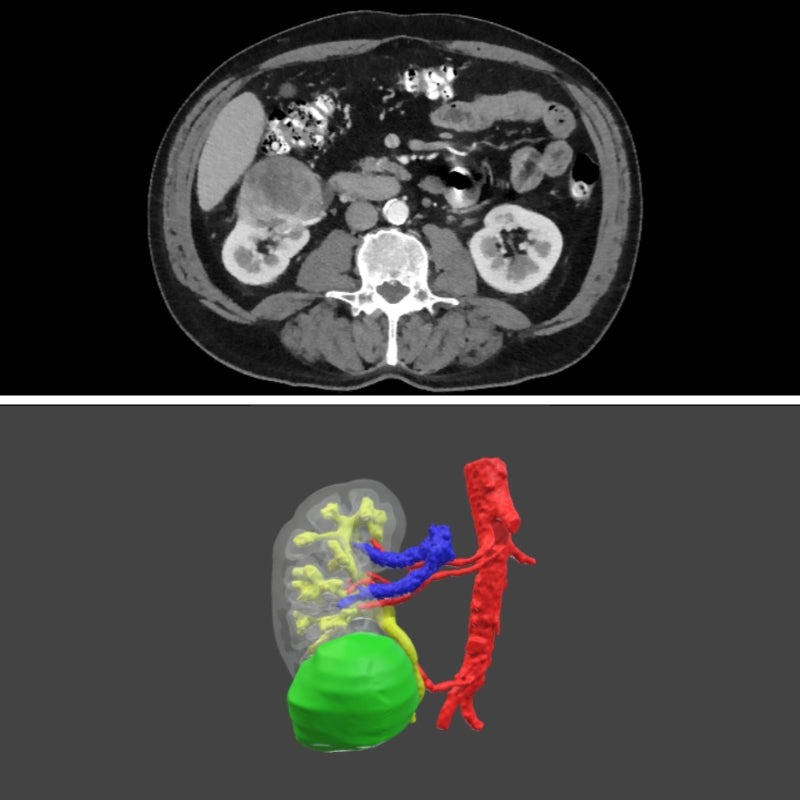

Surgical planning - Digital 3D model for urology

Surgical planning - digital model

Only for urology

Plan your next surgery with a 3D model of the patient's exact anatomy. This planning is done based on the CT scans.